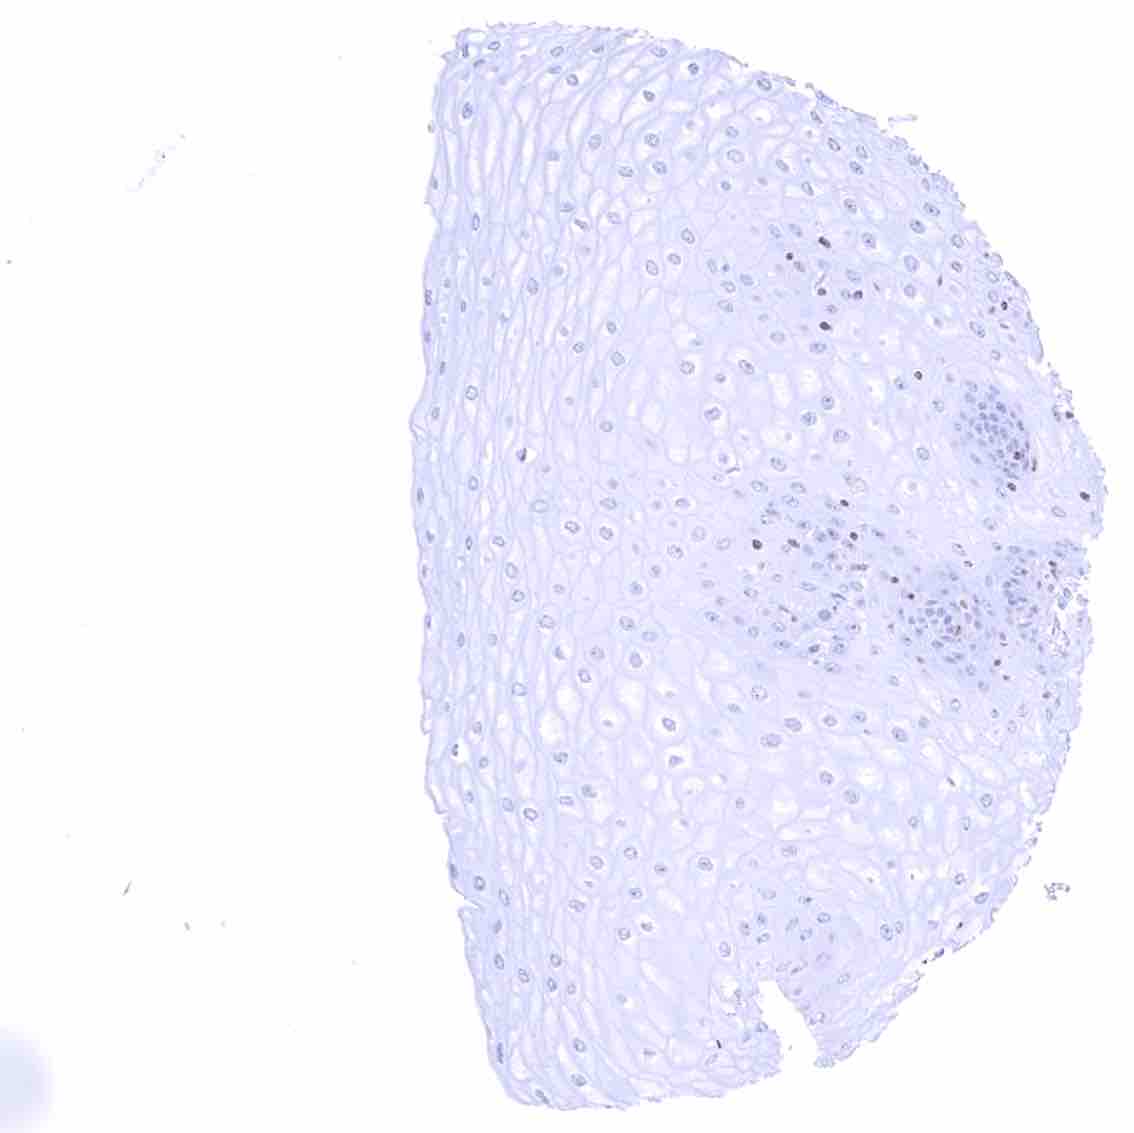

Tonsil –Strong bcl-2 positivity of large fraction of lymphocytic cells in the interfollicular area & around germinal centres. Cells in germinal centres are largely bcl-2 negative. Squamous epithelium with weak bcl-2 staining of the basal cell layer

Tonsil, surface epithelium